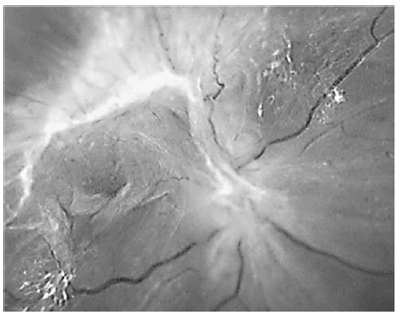

Acerca do descolamento de retina tracional mostrado na figura acima, assinale a alternativa correta.